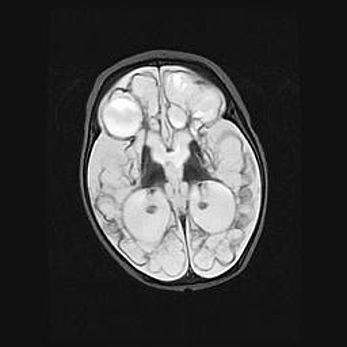

Наружная гидроцефалия с возможной атрофией височных областей.

Возраст: 28 дней

Вес: 3670 г

Пол: мужской

Окружность головы: 38 см

Срок гестации: 40 недель

Гидроцефалия головного мозга у новорожденных – это заболевание, которое характеризуется скоплением избыточного количества спинномозговой жидкости в желудочковой системе головного мозга в результате затруднения её перемещения от места выработки к месту поглощения в кровеносную систему или вследствие нарушения абсорбции. При открытой наружной форме гидроцефалии у новорожденных расширяются и переполняются субарахноидные пространства.

При нормотензивных  формах,  которые,  как  правило,  являются  следствием  перенесенных ишемических  повреждений  паренхимы  мозга,  возможно  сочетание микроцефалии  с нормотензивной гидроцефалией. В основе данных изменений лежит атрофия больших полушарий с преимущественной  локализацией  в  лобно-височных  областях.